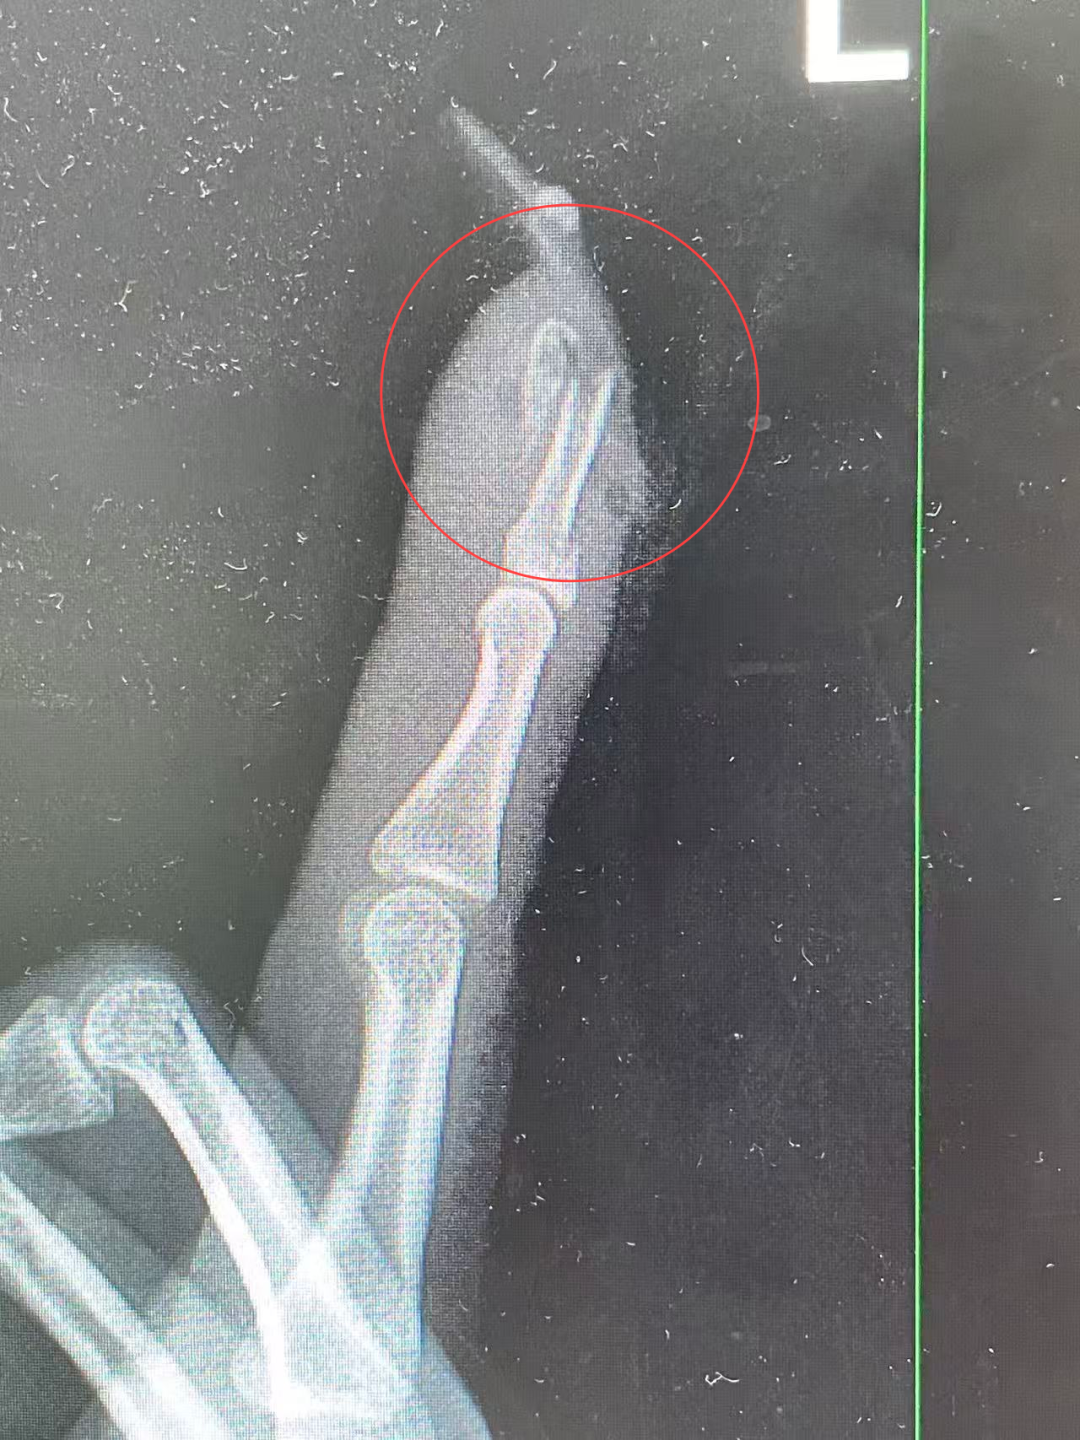

“左手食指指骨骨折,甲床闹翻,部分甲床外露,需要手术蛊卦。”接诊的曹立副主任大夫检讨后作出会诊,并当即对其作念了指骨骨折闭合复位内固定术。

王姑娘术前的X光影像

术后,王姑娘情况归附简易。